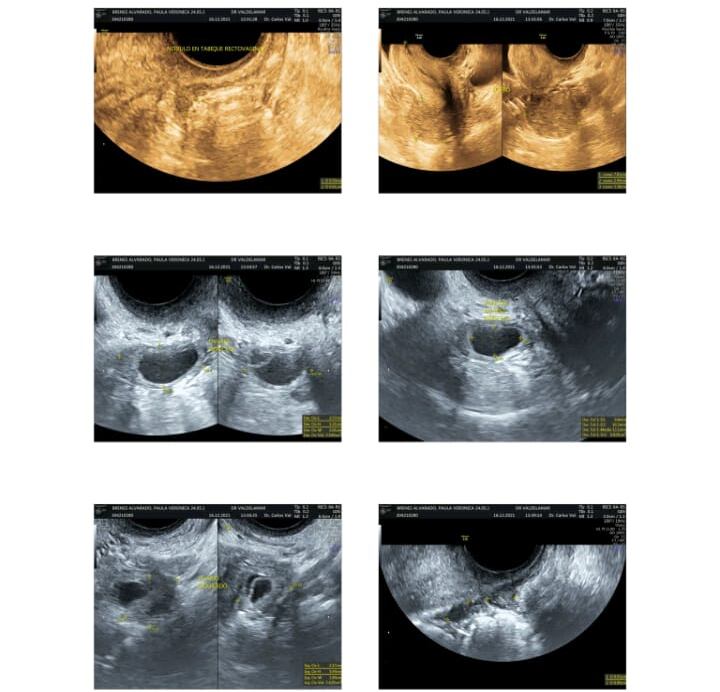

La joven cartaginesa tiene una endometriosis recto vaginal, con tres pelotitas que le producen fuertes dolores en toda el área del vientre y recto, al punto que deben incapacitarla porque no puede ni moverse.

“Lo mío ya no tiene cura, solo lo mantengo estabilizado con los medicamentos y el doctor Carlos Valdelamar (especialista en endometriosis) me dijo que no podía dejar de tomarlo, porque la enfermedad podría empeorar si lo hago. Aparte que mi salud y mi calidad de vida se están deteriorando”, explicó Paula.